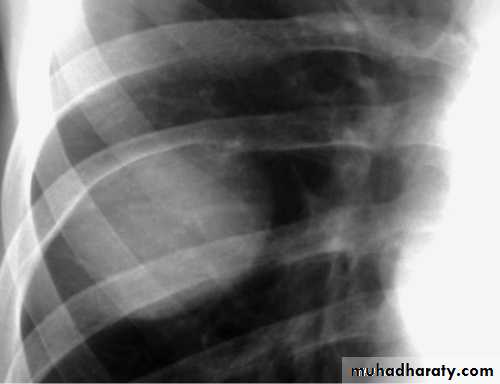

Fall from the 2nd floor